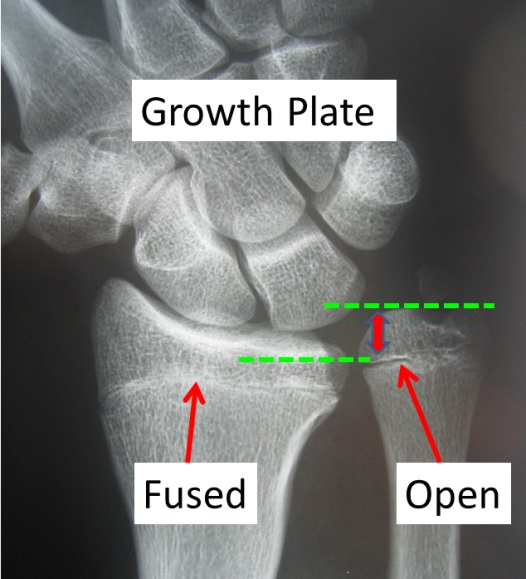

@unon I'm confused, are they trolling OP or notView attachment 4545367

What on earth are you guys talking about? They're very clearly open.

I've already made a guide on this OP,

The Radiology behind Facial Development & Bodily Growth Indicators; How to tell if you’re still growing.

The Radiology behind Facial Development & Bodily Growth Indicators By @Orka I've seen at least 50 questions asking if somebody's growth plates are still open or not, or to estimate their bone age,so to make it easy, here's how you can answer your own questions! Table Of Contents (easiest...looksmax.org

Feel free to verify for yourself if needed

Why do people answer questions when they're not able to provide an accurate answer? This is one of the simplest things to see for yourself and people still get it wrong

It's literally looking for a LINE, how do you mess that up.

Yes they r cleary open, i was also questioning myself why ppl said there were closedView attachment 4545367

What on earth are you guys talking about? They're very clearly open.

they r open but in the late stages of open and will close soonAre the growth plates open? And if so, to what extent?

Isn't that just the epiphyseal line / physeal scar?View attachment 4545367

There's no gap because he's a teenager, not a child, that's only present in children. You stop growing once it's fully ossifiedIsn't that just the epiphyseal line / physeal scar?

How old are you?thx bro, and please tell me, are they very open?

15There's no gap because he's a teenager, not a child, that's only present in children. You stop growing once it's fully ossified

View attachment 4545393

Something inbetween (like OP) is still growing

How old are you?

There's no gap because he's a teenager, not a child, that's only present in children. You stop growing once it's fully ossified

Something inbetween (like OP) is still growing